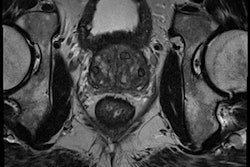

Investigators from Huazhong University of Science and Technology in Wuhan, China, and Yale University School of Medicine in the U.S. developed deep-learning software and compared its performance with a nondeep-learning method for differentiating prostate cancer from benign conditions such as benign prostatic hyperplasia (BPH) and prostatitis. In a study involving over 170 patients with over 2,600 prostate MR images, the group found the deep-learning software yielded significantly higher sensitivity and specificity.

Of the 172 patients included in the study, 79 had prostate cancer and 93 had benign conditions. The 93 benign cases included 75 with BPH and 18 with both BPH and prostatitis. The 172 patients had a total of 2,640 MR images.

The prostate MRI exams were performed on a Magnetom Skyra 3-tesla whole-body MRI scanner (Siemens Healthineers) using syngo MR D13 software, an 18-element body matrix coil, and a 32-element spine matrix coil. The acquisition protocol included T1- and T2-weighted images, along with diffusion-weighted images and dynamic contrast enhancement.